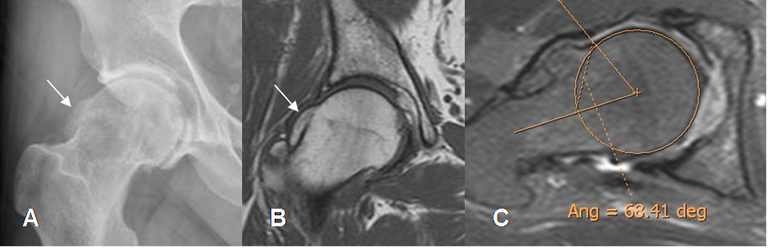

Fig 104. Pinzamiento tipo cam. Angulo alfa normal.

RM axial oblicua de cadera. Trazado entre el eje del cuello femoral y el sitio donde se corta la circunferencia de la cabeza femoral, con el borde lateral.

Fig 105. Pinzamiento tipo cam. Angulo alfa aumentado.

A: Rx AP de cadera y B: RM coronal en T1. Prominencia del borde lateral de la cabeza femoral, por pinzamiento tipo cam.

C: RM axial oblicua de cadera. Aumento del ángulo alfa, mayor de 55º.